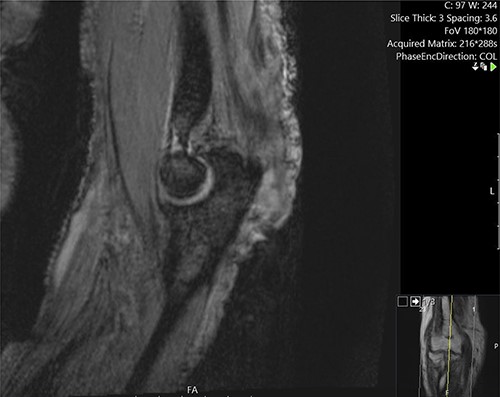

He was investigated with incisional biopsy of the lesion; four samples confirmed poorly differentiated cSCC. Further MRI imaging showed deep invasions of the cubital joint including, olecranon and ulna, and associated infiltration of the ulnar nerve and distal triceps (Figs 3 and 4). Positron emission tomography scan showed no distant metastases.

Sagittal MRI image demonstrating the invasion of the lesion into the, olecranon and distal triceps.